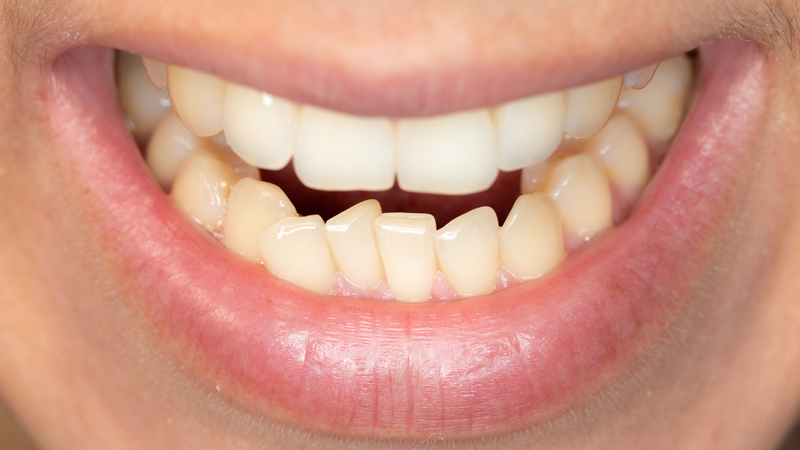

Răng móm (hay còn gọi là khớp cắn ngược) là tình trạng hàm dưới đưa ra trước so với hàm trên, khiến khi ngậm miệng lại, các răng dưới phủ ra ngoài răng trên. Đây là một dạng lệch khớp cắn loại III trong nha khoa, thường gặp ở cả trẻ em và người lớn.

Răng móm do răng xảy ra khi xương hàm phát triển bình thường, nhưng hướng mọc của răng bị lệch. Cụ thể, răng cửa dưới nghiêng ra trước hoặc răng cửa trên nghiêng vào trong, làm khớp cắn bị đảo ngược. Dạng này thường nhẹ, ít ảnh hưởng đến khuôn mặt và có thể điều trị hiệu quả bằng niềng răng chỉnh nha trong 1,5 - 3 năm.

Ngược lại, răng móm do xương hàm là tình trạng hàm dưới phát triển quá mức hoặc hàm trên kém phát triển, khiến toàn bộ cung răng dưới nằm phía trước cung răng trên. Dạng móm này ảnh hưởng rõ đến thẩm mỹ, khuôn mặt thường có cằm nhô, gò má thấp và có thể gây rối loạn khớp thái dương hàm. Điều trị chủ yếu là phẫu thuật chỉnh hàm, giúp tái lập lại tương quan giữa hai hàm, đôi khi kết hợp niềng răng để đạt khớp cắn chuẩn.